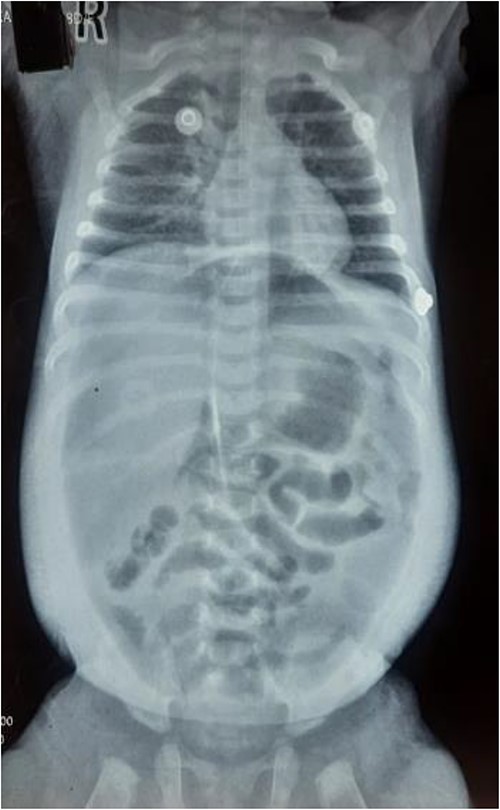

Upon arrival, we conducted a comprehensive medical history review and relevant physical examinations. The baby, delivered via Cesarean section due to fetal distress, had no major health issues except for her mother’s gestational diabetes and a second-trimester urinary tract infection, both managed conservatively. Initial examination indicated signs of dehydration, including a high heart rate, elevated respiratory rate, and 97% oxygen saturation with oxygen support. Abdominal examination revealed distention, visible veins, firmness, and absent bowel sounds. Respiratory and cardiovascular examinations were normal. An erect abdominal X-ray revealed pathological free gas under the right dome of the diaphragm, strongly suggesting a hollow viscus perforation as shown in Fig. 2. Routine blood tests were normal, with a slightly elevated CRP level at 9.5 mg/dl.

Erect X-ray showing pathological free gas under bilateral dome of diaphragm.